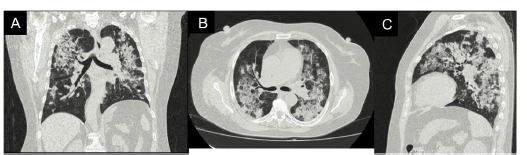

Figura 2 Tomografia de alta resolución de tórax proyección coronal (A), axial (B) y sagital (C). Engrasamiento de las paredes de la via aérea central y áreas de consolidación de distribución broncéntricas distribuidas en ambos pulmones, algunas asociadas con áreas de vidrio esmerilado.

El compromiso combinado pulmonar y renal por algunas de estas enfermedades también está descrito como síndrome pulmón-rinón18. Cuando se sospecha VAA en el contexto de SS, la tomografía de alta resolución a menudo determina el patrón predominante de lesión. De ellas, la neumonía en organización es la más comúnmente vista19. Otra anormalidad que se puede presentar es la hemorragia alveolar, la cual se puede manifestar como masas de tamaño variable con o sin signo del halo (hemorragia perinodular)20.